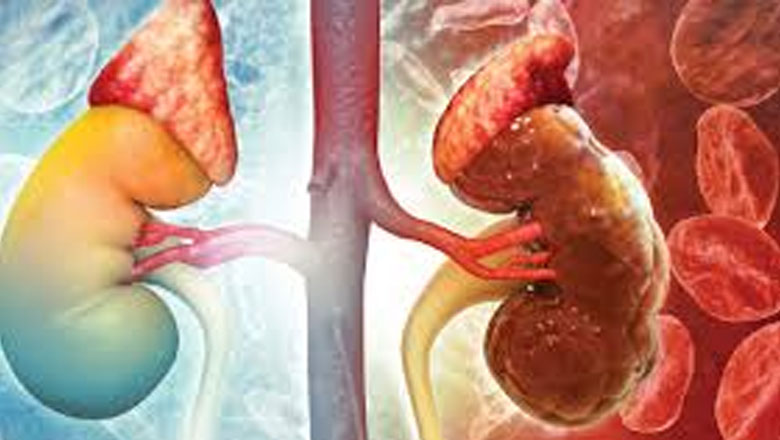

വൃക്ക തകരാര് സാധ്യത ആരിലൊക്കെ?

നിങ്ങളുടെ വൃക്കകളുടെ പ്രവര്ത്തനം ശരിയായ രീതിയിലാണോ എന്ന വിലയിരുത്തൽ, മുന്കൂട്ടിയുള്ള രോഗനിര്ണയത്തിന്റെ പ്രാധാന്യം, വൃക്കകളുടെ സംരക്ഷണം- ഈ മൂന്ന് ആശയങ്ങൾ വളരെ അർഥ പൂർണമാണ്. കാരണം, നമ്മുടെ ശരീരത്തിലെ സുപ്രധാന അവയവങ്ങളില് വൃക്കകളും ഉള്പ്പെടുന്നു. വൃക്കകള്ക്ക് തകരാർ സംഭവിച്ചാല് അതു ജീവിതനിലവാരത്തെ പ്രതികൂലമായി ബാധിക്കുന്നു. കൂടാതെ, വൃക്കകളുടെ ചികിത്സ ചെലവേറിയതാണ്. രോഗലക്ഷണങ്ങൾ എപ്പോൾ?75% വൃക്ക തകരാര് സംഭവിച്ചശേഷം മാത്രമാണ് രോഗലക്ഷണങ്ങള് പ്രകടമാകുന്നത്. അതിനാല് വൃക്കയുടെ ആരോഗ്യം നിര്ണയിക്കുന്നതില് രോഗലക്ഷണങ്ങള് പ്രധാന പങ്കു വഹിക്കുന്നില്ല. വൃക്ക തകരാറിനു സാധ്യത കൂടുതലുള്ളവരില് മുന്കൂട്ടി ചില പരിശോധനകള് ചെയ്യേണ്ടതാണ്. വൃക്ക തകരാര് സാധ്യത· പ്രമേഹ രോഗികള്/ഡയബറ്റിസ് മെലിറ്റസ് ഉള്ള 40% രോഗികള്ക്ക് വൃക്ക സംബന്ധമായ പ്രശ്നങ്ങള് ഉണ്ടാകാന് സാധ്യത കൂടുതലാണ്. · അമിത രക്തസമ്മര്ദം ഉള്ളവരില്.· ഗ്ലോമെറുലാർ നെഫ്രൈറ്റിസ് (Glomerular Nephritis) ബാധിച്ചവര്ക്ക് അല്ലെങ്കില് മൂത്രത്തില് രക്തമയം, പ്രോട്ടീനൂറിയ വന്നവര്ക്ക് ഭാവിയില്…